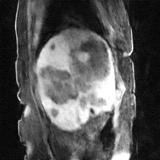

Deep neural networks for medical image reconstruction are traditionally trained using high-quality ground-truth images as training targets. Recent work onNoise2Noise (N2N) has shown the potential of using multiple noisy measurements of the same object as an alternative to having a ground truth. However, existing N2N-based methods cannot exploit information from various motion states, limiting their ability to learn on moving objects. This paper addresses this issue by proposing a novel motion-compensated deep image reconstruction (MoDIR) method that can use information from several unregistered and noisy measurements for training. MoDIR deals with object motion by including a deep registration module jointly trained with the deep reconstruction network without any ground-truth supervision. We validate MoDIR on both simulated and experimentally collected magnetic resonance imaging (MRI) data and show that it significantly improves imaging quality.